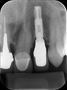

Radiografia Interproximal

O objetivo principal desta técnica é o exame das faces proximais dos dentes posteriores e da crista óssea alveolar. É indicado na detecção de processos cariosos, adaptações marginais de restaurações e presença de lesões periodontais, que apresentem comprometimento de estruturas ósseas, com destruição da crista óssea alveolar.